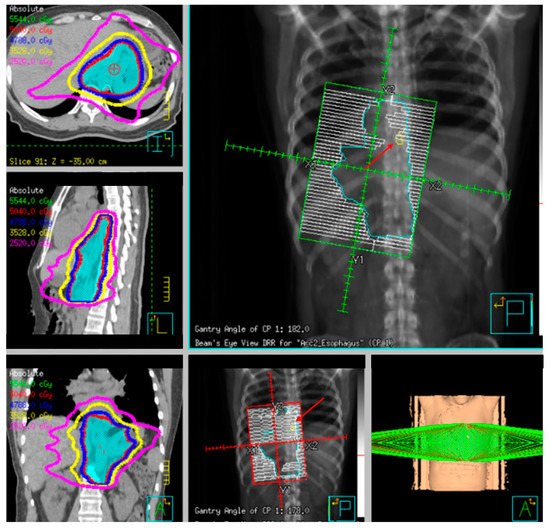

Three-dimensional conformal planning for radiation therapy can be utilized; however, more institutions have implemented intensity-modulated radiation therapy (IMRT) to reduce cardiac and lung dosing, which allows for a simultaneous integrated boost (SIB) or sequential boost techniques [73][74][75]. This approach is important as cardiac dose is increasingly seen as an independent risk factor for reduced survival [76] and has been correlated with excess G3+ cardiac toxicity [77][78].

Fiducial markers can be placed endoscopically to delineate the extent of disease with high technical success with a small risk of migration [79][80][81]. Stable fiducial markers improve the reliability of target volume delineation and assessment of respiratory tumor motion with four-dimensional CT (4D-CT) simulation as a direct visual correlate of tumor extent. Combined with fused PET/CT, fiducials reduce the margins for treatment planning due to improved confidence of accurately defined gross tumor volumes (GTVs) [82] and facilitate daily image-guided radiation therapy (IGRT) during treatment [83], see Figure 7 and Figure 8. Moreover, 4D-CT imaging at simulation has a greater benefit in GEJ and gastric tumors due to the propensity of respiratory motion [84] and aids in internal target volume construction and planning target volume expansions during treatment planning. Radiation treatments generally are conventionally fractionated (1.8–2.0 Gy daily); however, previously mentioned SIB techniques treating at 2.2–2.25 Gy daily can push dose to gross disease past 60 Gy. If given sequential neoadjuvant chemotherapy, the extent of original disease is often included in the clinical target volume receiving 4500–5040 cGy and boost is only directed to residual gross disease. Clinical target volumes extend 3–4 cm craniocaudal and 1 cm radially and are edited off anatomical structures that are clinically uninvolved such as vertebral bodies, trachea, aorta, lung, and pericardium. For middle and upper thoracic tumors, the at-risk periesophageal and adjacent mediastinal lymph nodes and, for distal esophageal and GEJ tumors, the celiac lymph nodes are covered. Multi-institutional consensus contouring guidelines for IMRT in esophageal and gastroesophageal tumors have been published [85].

Figure 8. Example radiotherapy plan for image-guided treatment with fiducial contoured (red arrow) and within the planning target volume (PTV).